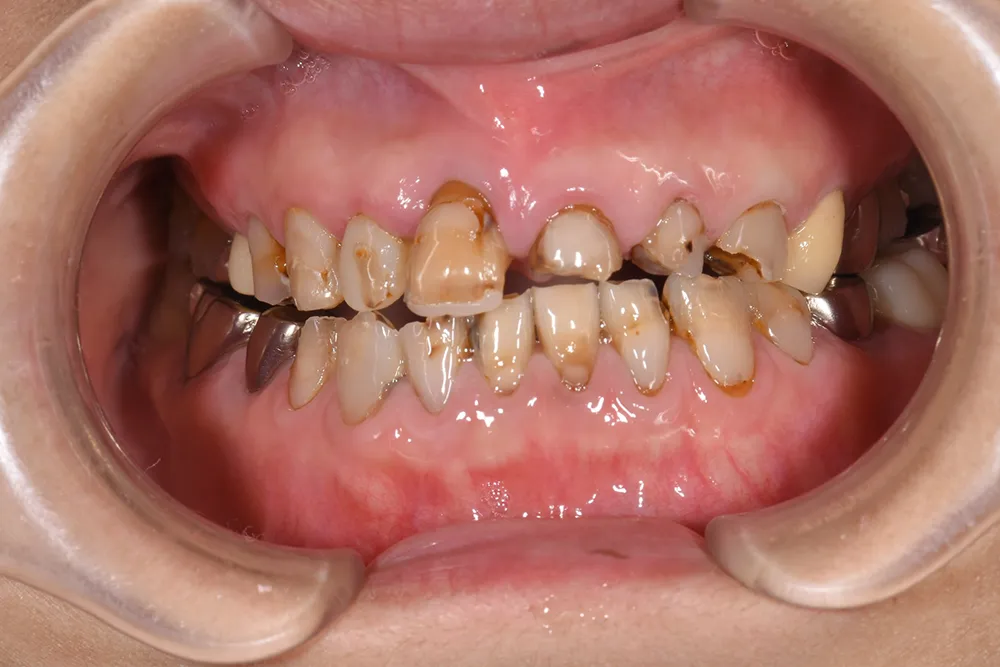

主訴 かみ合わせの機能障害と見た目の審美性を高めたい

治療方法 全顎をオールセラミック補綴で治療

治療期間 約1.5年

通院回数等 30回

費用 4,004,000円(税込)

リスク・副作用 治療期間が長くなる